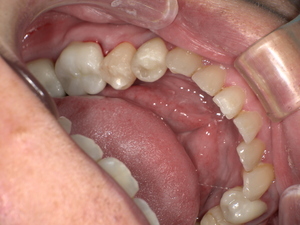

Before:白い詰め物がとれて、見た目も清潔感に欠ける状態。

After: セラミックで修復され、天然歯のように自然な白さと透明感がある美しい歯の状態。どこが治療箇所か分からないほど自然な白さへ。